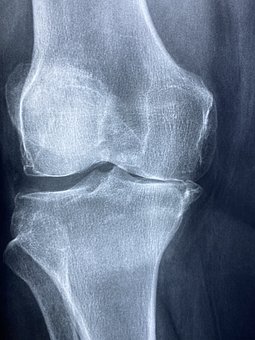

무릎 퇴행성 관절염은 말 그대로 무릎연골이 닳아 없어지면서 뼈끼리 부딪히게 되고 이로 인해 염증반응이 일어나 통증이 생기는 질환입니다.

무릎 관절은 야외활동이 늘어나는 봄은 무릎 관절 건강관리에 각별한 신경을 쓰는 시기입니다. 겨울 내내 뻣뻣해지고 힘이 빠진 무릎 관절이 갑작스러운 스트레칭으로 손상될 수 있기 때문입니다. 무릎 관절염은 무릎 위아래 뼈 사이 연골이 닳아 관절에 염증이 생기는 질환입니다. 무릎 연골은 관절에 가해지는 충격을 흡수해 통증 없이 관절이 원활하게 움직이도록 도와줍니다. 이러한 무릎 연골은 노화, 지속적인 충격, 체중 부담 등으로 인해 점차 마모되어 질병에 걸릴 위험이 높아집니다. 통증이나 삐걱거리는 느낌, 마찰음 등이 무릎 관절염의 주요 증상입니다.

무릎 관절의 무릎 퇴행성 관절염의 진행 단계는 연골의 손상 정도에 따라 크게 4단계로 나눌 수 있습니다.

1 단계 증상이 시작돼 시큰한 통증이 생기지만 누워있거나 앉아서 쉬면 통증이 가라앉습니다.

2 단계 연골이 손상돼 무릎 관절 사이 간격이 좁아지면 염증이 생겨 무릎을 자유롭게 구부리고 펴기가 어렵습니다.

3 단계 증상은 뾰족한 뼈가 가시처럼 자라는 뼈가 있어어'골절'이 잇따라 발생해 통증이 자주 발생합니다.

4 단계말기 단계로 증상이 악화되면 연골 손상이 심하고 무릎 위아래 뼈가 거의 닿아 극심한 통증과 발열을 동반합니다. 한번 손상된 연골은 회복이 어려운 것이 사실입니다. 다만, 초,중반까지는 비수술적 치료를 통해 증상 개선을 기대할 수 있습니다. 따라서 의심 증상이 발생할 경우 조기에 전문의를 찾아 정확한 진단과 관리를 받는 것이 증상악화를 줄이는 무릎 퇴행성 관절염 치료의 핵심입니다.